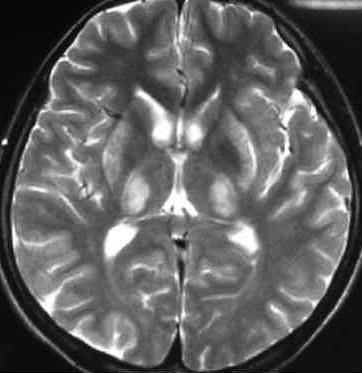

核磁:

磁共振可以随意做任何角度的切层,且无辐射。对颅脑、脊柱和脊髓等的解剖和病变的显示,都比CT要好;核磁共振对病变组织的敏感度优于CT,尤其是关节、肌肉、中枢神经系统等软组织的检查结构更清晰。核磁共振对脊柱、关节、肿瘤、感染性疾病、淋巴结和血管结构之间的相互鉴别,有独到的优势。